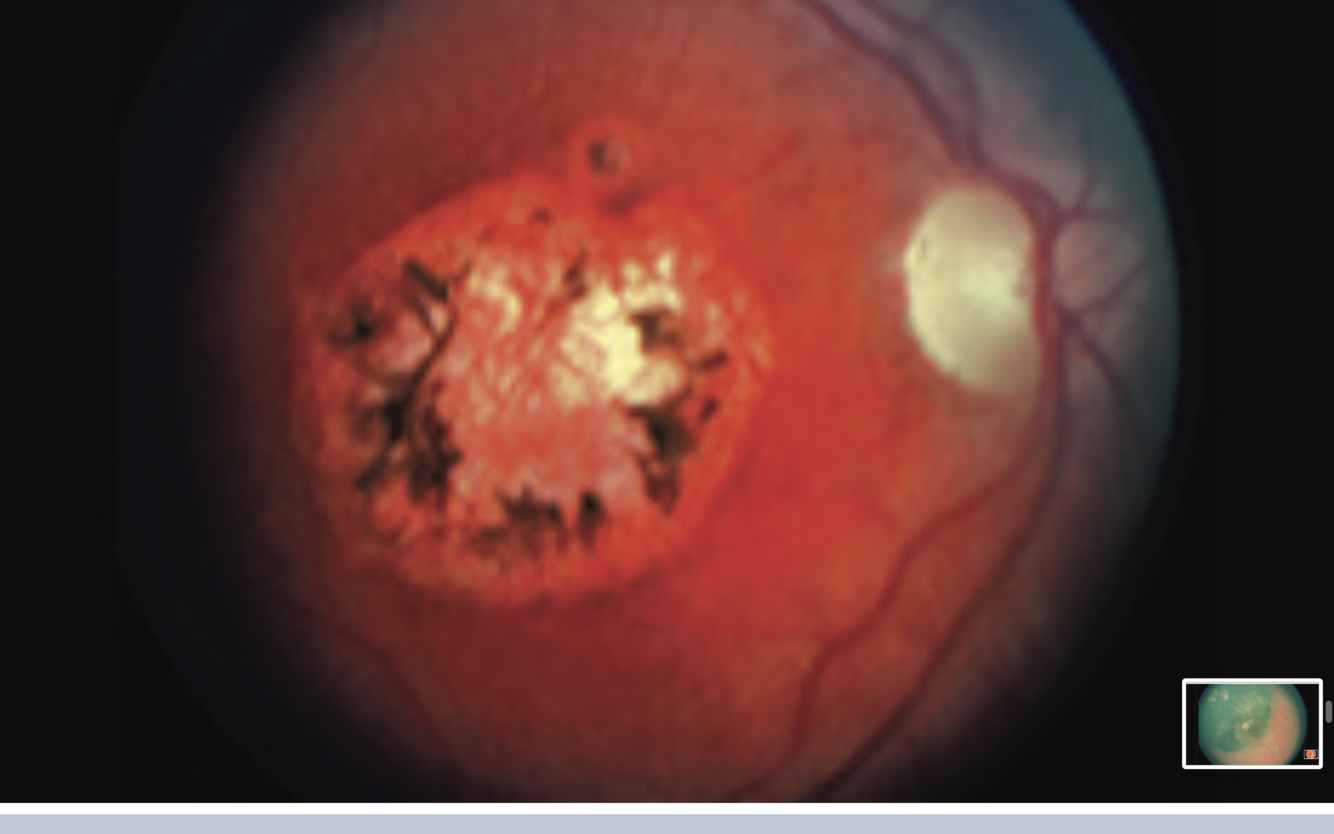

Retinitis Pigmentosa

- multiple bony spicule retinal pigmentation scattered around retina periphery